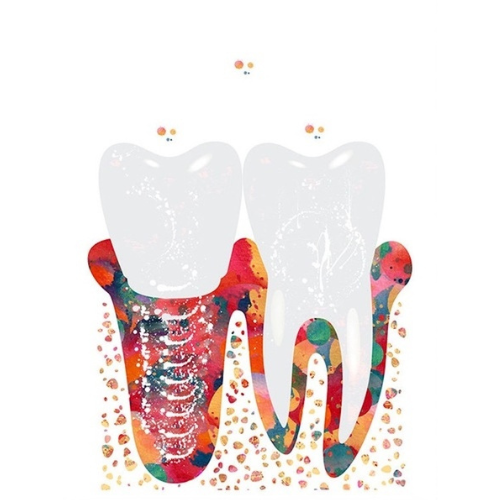

La résection apicale